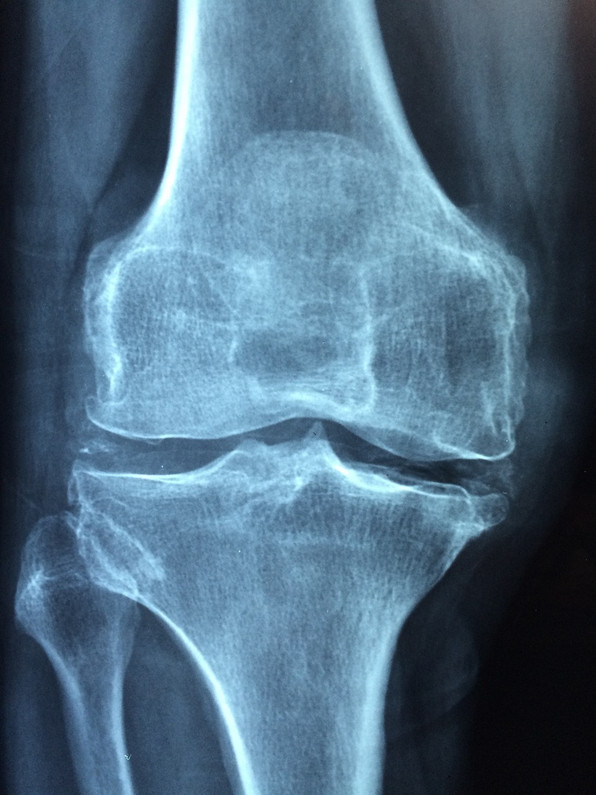

According to some statistics, more than 50 million people in the US live with osteoporosis, a disease that weakens your bones by making them thinner and less dense than they should be. The likelihood of developing osteoporosis increases significantly as you age, affecting the ability of your bones to absorb impact. While it’s natural for your bones to lose some of their density over the years, with osteoporosis the fragility of your bones begins to pose a very real danger.

“Maca helps make bones harder,” explains Dr. Cassie Wilder, a registered naturopathic doctor. While it’s not to be used in place of Vitamin D or calcium, research has found links between consumption of maca root and improvements in bone mass. A 2006 study on the effects of regular maca consumption by postmenopausal women found that subjects who had taken maca for four months demonstrated noticeably increased bone density markers.

In 2010, researchers studying the effects of different varieties of maca on the bone structure of lab rats found that red and black maca root exhibited protective effects on bone architecture in the rats. This seemed to predict a research trend, with a 2015 study making similar conclusions: that maca root contains certain “physiologically-effective” components which act in preventing osteoporosis.